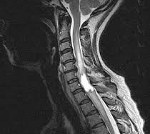

Ранее диагностика спинальных новообразований осуществлялась при помощи миелографии. В настоящее время на смену ей пришли томографические методы нейровизуализации. Использование КТ позвоночника позволяет дифференцировать интрамедуллярные опухоли спинного мозга с его кистами, гематомиелией и сирингомиелией; диагностировать сдавление спинного мозга. Но наиболее информативным способом диагностики спинальных опухолей на сегодняшний день выступает МРТ позвоночника.

МРТ позволяет предположить тип опухоли, определить ее диффузный или фокальный характер, установить точную локализацию и распространенность. Все эти данные необходимы не только с диагностической точки зрения, но и для адекватного планирования хирургического лечения. Т1-режим более информативен в отношении кистозных и солидных составляющих новообразования, Т2-режим — в отношении кист и визуализации цереброспинальной жидкости. Применение контраста значительно облегчает дифференцировку опухоли от окружающих ее отечных тканей.